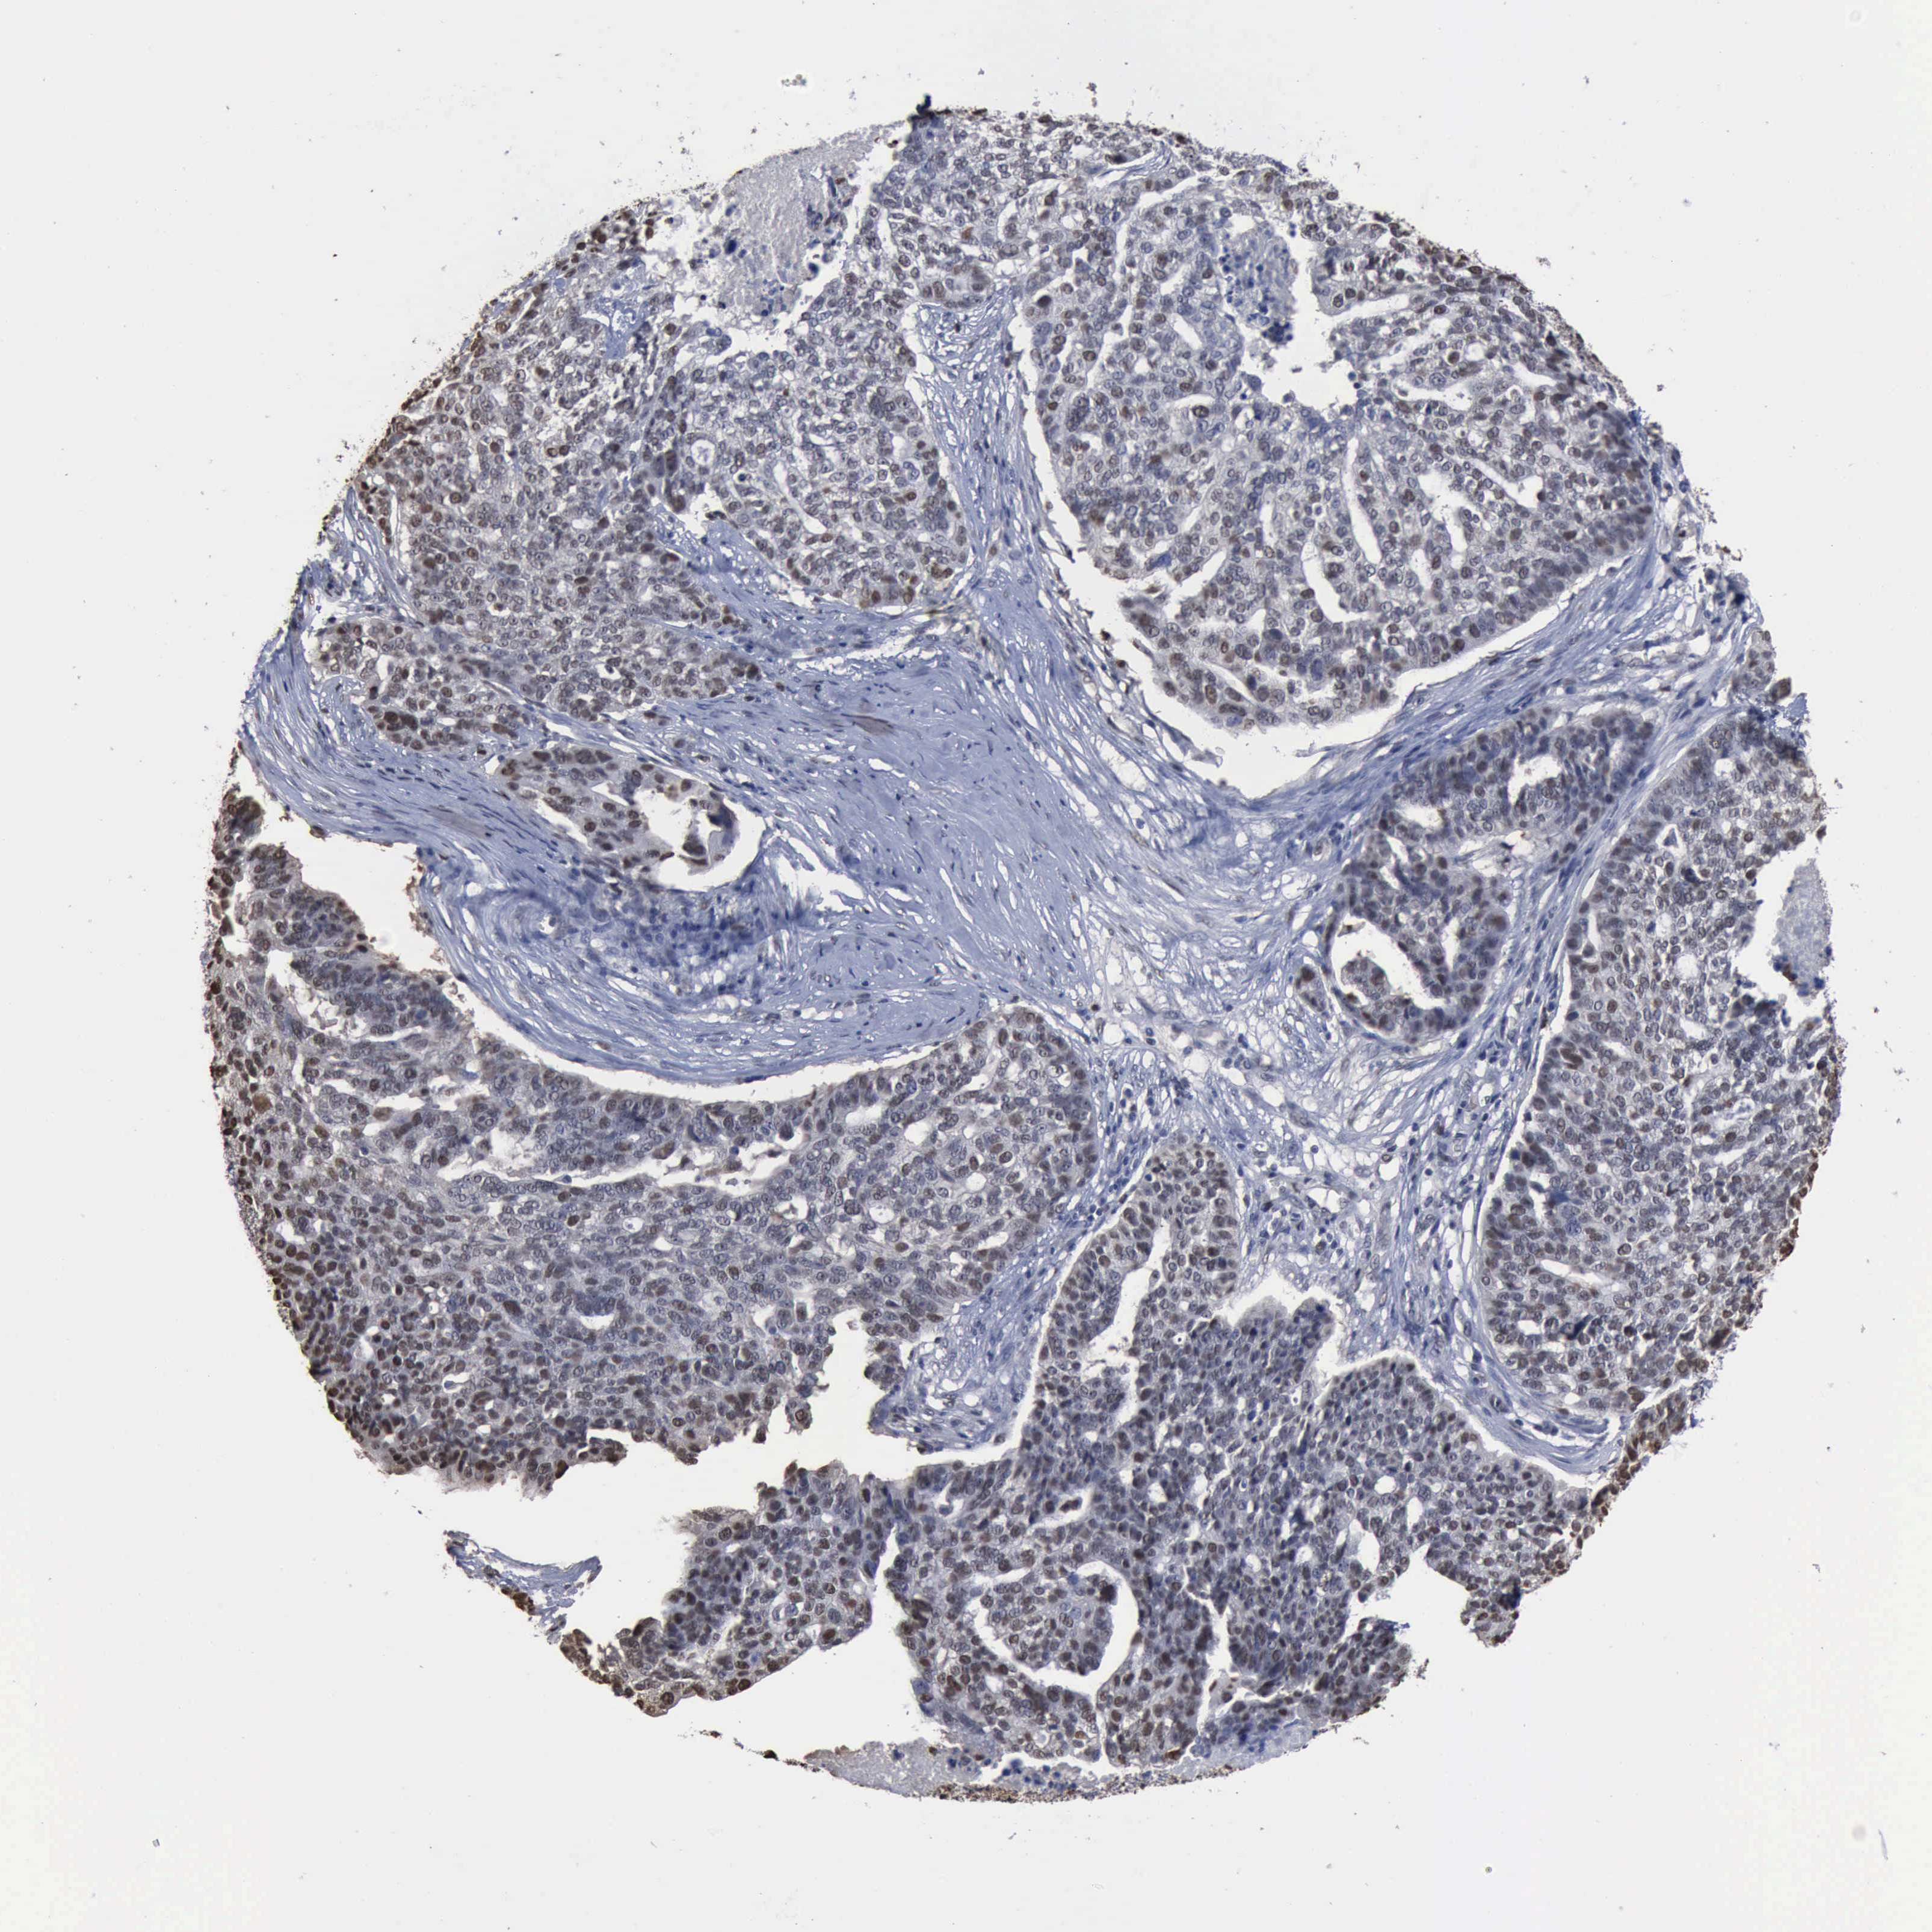

OVARIAN CANCER - Protein expressioni

A mouse-over function shows sample information and annotation data. Click on an image to view it in a full screen mode. Samples can be filtered based on level of antibody staining by selecting one or several of the following categories: high, medium, low and not detected. The assay and annotation is described here.

Note that samples used for immunohistochemistry by the Human Protein Atlas do not correspond to samples in the TCGA dataset.

Antibody stainingi

Antibody staining in the annotated cell types in the current human tissue is reported as not detected, low, medium, or high, based on conventional immunohistochemistry profiling in selected tissues. This score is based on the combination of the staining intensity and fraction of stained cells.

Each image is clickable and will lead to virtual microscopy that enables deeper exploration of all samples and also displays staining intensity scores, fraction scores and subcellular localization as well as patient and tissue information for each sample.

HPA030521

Cystadenocarcinoma, serous, NOS